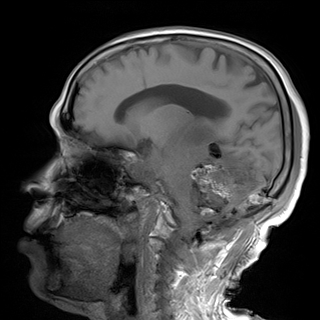

Brain MRI Brain Tumor Detection Analysis Dataset

This dataset is a brain MRI dataset for tumor detection and analysis, containing high-quality multi-sequence brain MRI scans from different patients. These scans contain T1-weighted (pre- and post-contrast), T2-weighted, FLAIR, and diffusion-weighted imaging (DWI) sequences. This dataset covers multiple types of brain tumors, such as gliomas, meningiomas, pituitary tumors, and metastases, and is compared with healthy controls, making it suitable for the development and validation of any advanced machine learning models and clinical research applications.

Dataset Example